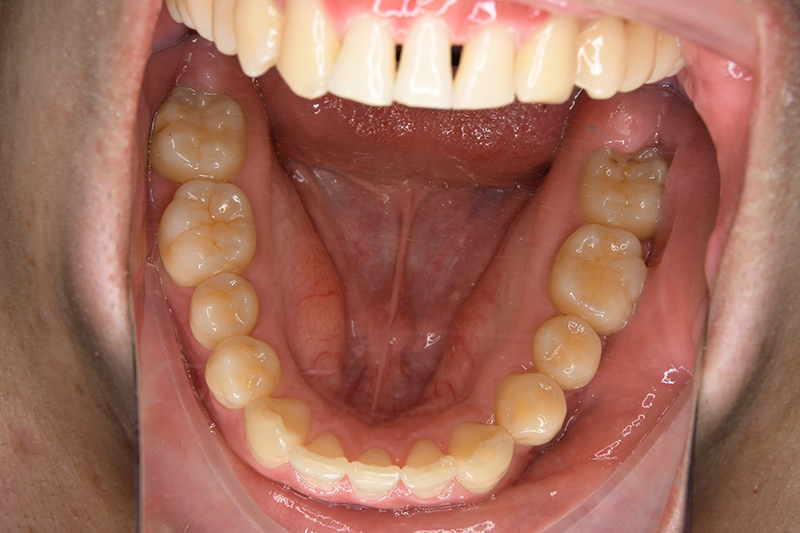

動的治療終了時

批評・予后 左側臼歯uprightによって鋏状咬合、過蓋咬合の改善が得られた。下顎前歯先欠によるAnterior ratio不調和と上顎前歯部叢生の改善を目的とし、上顎前歯にIPRを行ったが、治療後において左上2付近のover jetが大きく、上顎犬 歯間幅径の拡大(1.5mm)も生じているため、後戻りの懸念が残る。口元や歯列の安定性を考慮し、小臼歯抜歯も検討したがハイアングルであり下顎3-incisalのため、治療が困難となる事を危惧して非抜歯にて治療を行った。